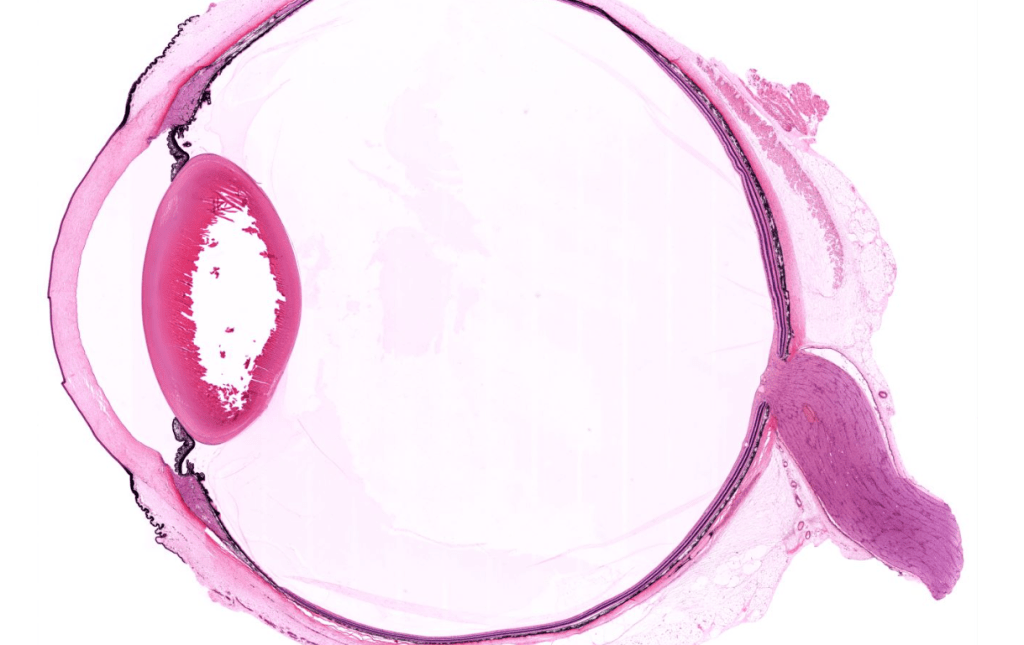

CÓRNEA

IRIS

CUERPO CILIAR

RETINA

CRISTALINO